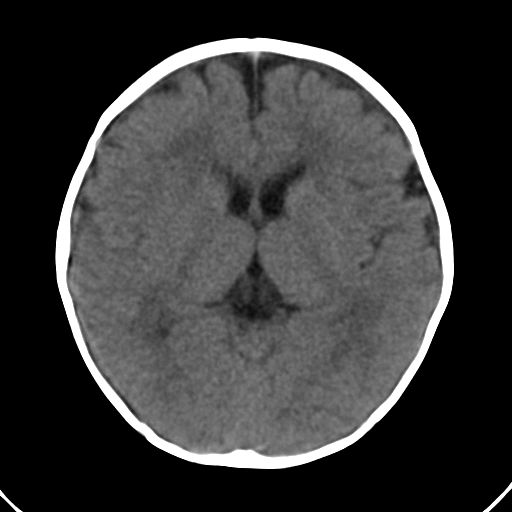

男,10月,足月剖腹产,无缺氧病史,当时评分均正常,学走路时脚后跟不着地!

小孩子片子,看得少,请各位老师看看有问题没?

未见明显异常。

外部性脑积水

考虑外部性脑积水

双侧脑鹅叶发育不良.

未见异常,10个月学走路是不是早了一点?脚后跟不着地可能是害怕或重心不稳,等等,14个月后看看。

轻度脑外脑积水表现.